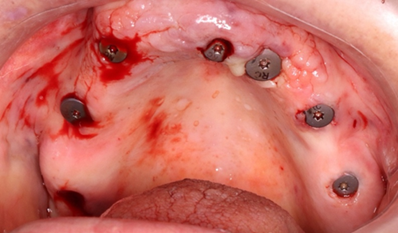

We follow the drilling protocol provided to place the implants with copious irrigation with saline solution and we finish by placement of the healing without sutures (Figure 23).

Figure 23: 7 healing screws placed.